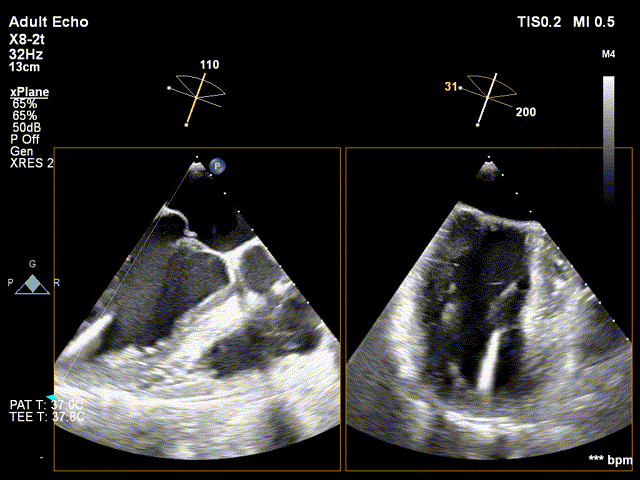

DMR:二尖瓣重度反流5+,P2区脱垂连枷,AP:38mm,MVA:6cm²,反流宽度14.2mm,反流2区,P2区脱垂范围14mm,连枷间距4mm,脱垂高度6.6mm,瓣环直径37mm。

全麻后,首先在心前区的肋间切开3-4CM小切口,暴露心脏的心尖位置,心尖穿刺后进入导丝,利用导丝交换导管鞘完成通路建立。将系统送入左心房,顺利到达二尖瓣病变区域。在经食道超声引导下,术者通过反复评估二尖瓣反流位置、抓捕位置、反流程度,在2区主动脉瓣与二尖瓣闭合线垂直进行巧妙夹合,最终植入一枚ValveClamp®MVC-Ⅲf夹。超声评估夹子固定良好,组织桥完整,无葫芦征,位置、轴向均符合预期。患者术后反流程度从大量转至少量,手术取得圆满成功。患者恢复良好,已经顺利出院。

捕获瓣叶,进行夹合 3D切面调整位置及钟向